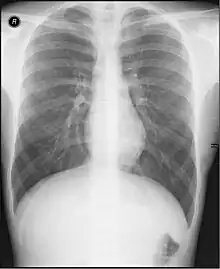

An X-Ray of Thoracic Region

Radiology (/ˌrdɪˈɒləi/ rey-dee-ol-uh-jee) is the medical specialty that uses medical imaging to diagnose diseases and guide treatment within the bodies of humans and other animals. It began with radiography (which is why its name has a root referring to radiation), but today it includes all imaging modalities. This includes technologies that use no ionizing electromagnetic radiation, such as ultrasonography and magnetic resonance imaging (MRI), as well as others that do use radiation, such as computed tomography (CT), fluoroscopy, and nuclear medicine including positron emission tomography (PET). Interventional radiology is the performance of usually minimally invasive medical procedures with the guidance of imaging technologies such as those mentioned above.

The modern practice of radiology involves a team of several different healthcare professionals. A radiologist, who is a medical doctor with specialized post-graduate training, interprets medical images, communicates these findings to other physicians through reports or verbal communication, and uses imaging to perform minimally invasive medical procedures[1][2] The nurse is involved in the care of patients before and after imaging or procedures, including administration of medications, monitoring of vital signs and monitoring of sedated patients.[3] The radiographer, also known as a "radiologic technologist" in some countries such as the United States and Canada, is a specially trained healthcare professional that uses sophisticated technology and positioning techniques to produce medical images for the radiologist to interpret. Depending on the individual's training and country of practice, the radiographer may specialize in one of the above-mentioned imaging modalities or have expanded roles in image reporting.[4]